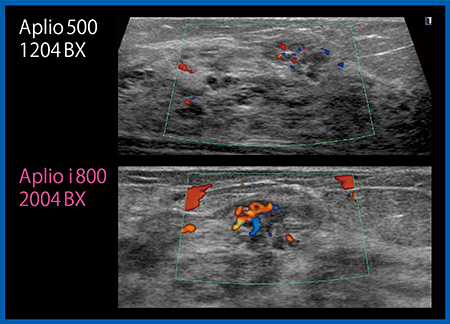

Aplio iシリーズでは,血流イメージの分解能も向上している。カラードプラを従来機と比較すると,より細い血管まで描出することが可能になっている(図3)。

図3 カラードプラの画像比較